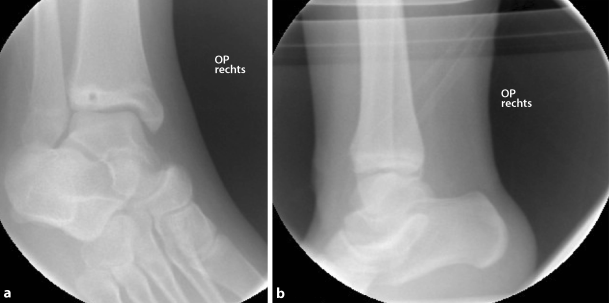

An exemplary case of a 14-year-old patient with a surgically treated Tillaux fracture is presented in Figs. 2 to 5 (Fig. 2a, b, X‑ray; Fig. 3a, b, CT scan; Fig. 4a, b, X‑ray after open reduction and screw fixation; Fig. 5a, b, X‑ray in two planes after screw removal).

Fig. 4

X-ray in two planes after open reduction and screw fixation in a 14-year-old patient (a anteroposterior view, b lateral view)

Bild vergrößern